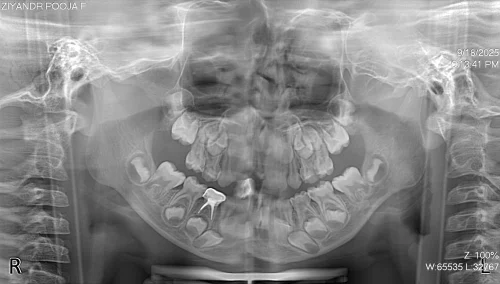

In this case, Dr. Pooja, a pediatric dental specialist at Magnum Clinic Dubai, checked a 5-year-old, Chinese school girl experiencing pain in the lower right primary molar.

The pulpectomy procedure was successfully completed by the use of the behavior management techniques, rotary pediatric files and the use of stainless steel crown restoration. This approach preserved the natural tooth, managed space, and prevented premature extraction.

The tooth had a severe infection. The plan was to remove the infected pulp (pulpectomy). The canals were cleaned with small rotary files. They were filled with a safe, resorbable paste (Metapex). A stainless steel crown was placed to protect the tooth and restore chewing.

Day 2: Remove pulp, clean canals, and fill them with Metapex.

The child was calmed using the Tell-Show-Do method. Numbing gel and a local shot made the area pain-free. A rubber dam kept the tooth dry and clean. The decay was removed. The infected pulp was taken out. The canals were cleaned and filled. A stainless steel crown was fitted and cemented.